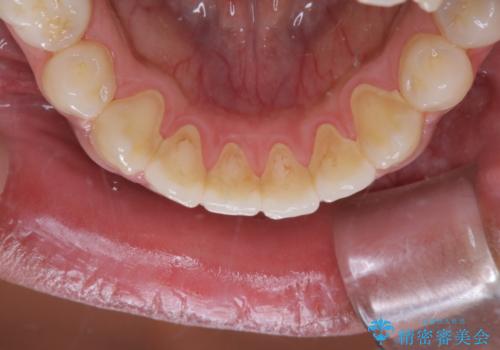

- 10年ぶりに歯科医院に来院された方です。クリーニングは人生で初めてとのことでした。

全体的に着色と汚れの量が多いため、PMTC60分コースで行いました。

歯石や着色、古くから蓄積した汚れは日常の歯ブラシではとることが出来ません。